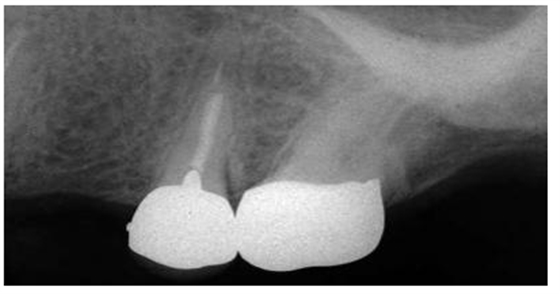

圖3:上頜第二前磨牙,牙根里非常短的樁

盡管短樁從未被提倡使用,但是研究發(fā)現(xiàn)經(jīng)常能在根尖片上觀察到短樁的存在(圖 3)。臨床上發(fā)現(xiàn)在327例樁修復(fù)當中,僅僅有34%的樁長度與冠上切-頸長度相當,即冠與樁長度的比例為1:1。一項研究曾對200例牙髓治療后的牙齒進行評估,結(jié)果顯示僅僅14%的樁長度為牙根長度的2/3或者長于牙根長度的2/3。另外一項根尖片研究結(jié)果表明樁修復(fù)中,樁長度為牙根長度的2/3或者3/4的比例僅占5%。當臨床上應(yīng)用短樁修復(fù)時,由于高應(yīng)力的原因,牙根常常會發(fā)生折斷,反之,增加樁的長度能夠提高牙根的抗折能力。